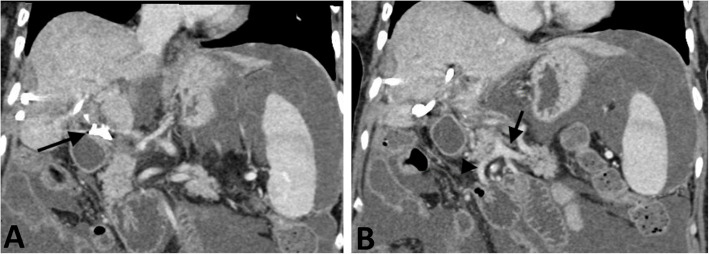

腹腔镜胆囊切除术治疗急性胆囊炎是最常用的手术之一,通常被认为是一种安全的手术,并发症风险低。血管和胆道损伤很少见,但后果严重。目前还没有进行系统的研究来描述这些情况下的最佳治疗策略,这些策略通常是根据具体情况进行管理的。本报告描述了一例患者行腹腔镜胆囊切除术,并发胆总管和门静脉主干结扎,导致肝梗死、肝周脓肿、门静脉高压合并腹水和门脉性充血性肠病。本病例的重点是处理该患者的血管损伤,并成功地通过经脾和右颈内静脉进入血管内门静脉重建。

Laparoscopic cholecystectomy for acute cholecystitis is one of the most performed surgeries and is generally regarded as a safe procedure with a low risk of complications. Vascular and biliary injuries are rare but have severe consequences. No systematic studies have been performed to delineate optimal treatment strategies in these scenarios, which are typically managed on a case-by-case basis. The present report describes a patient who underwent a laparoscopic cholecystectomy, complicated by common bile duct and main portal vein ligation, resulting in hepatic infarcts, perihepatic abscess, and portal hypertension with ascites and portomesenteric congestive enteropathy. This case focuses on management of this patient's vascular injury, which was successfully treated by endovascular portal venous reconstruction using trans-splenic and right internal jugular vein access.